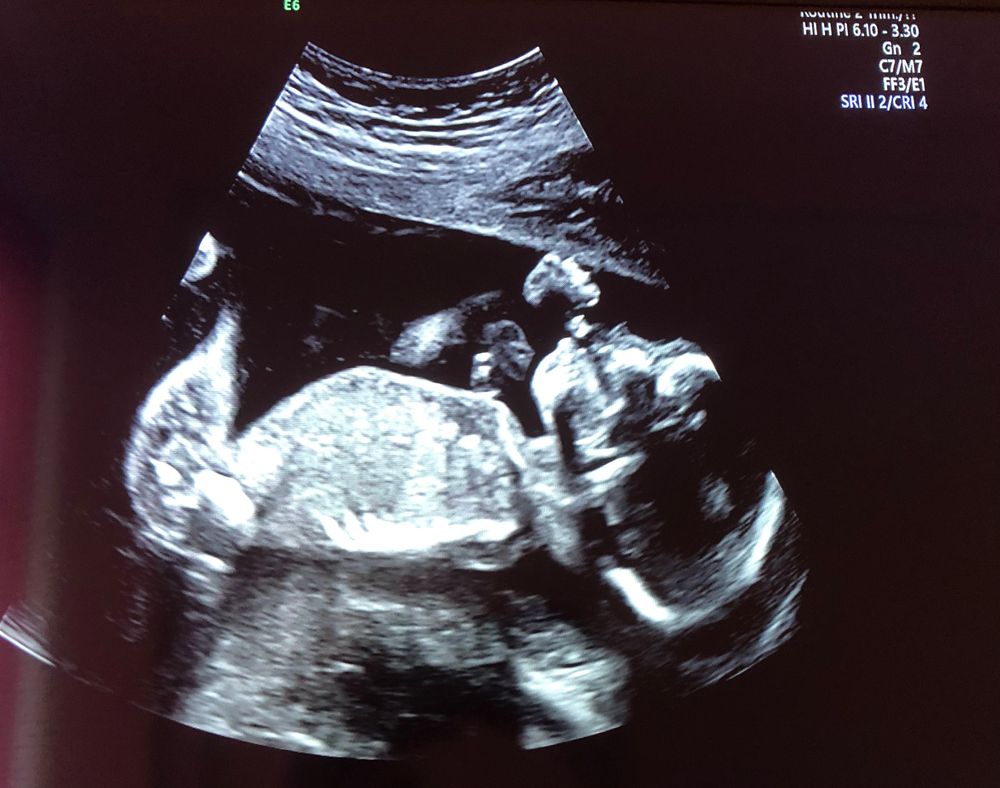

🤰🏻Беременность по счету - первая

🙆🏻 Предлежание - головное (с самого начала)

🐍 Обвитие - нет

👶 Пол - девочка

📏 Рост - 51см

⚖️ Вес - 3.290 кг